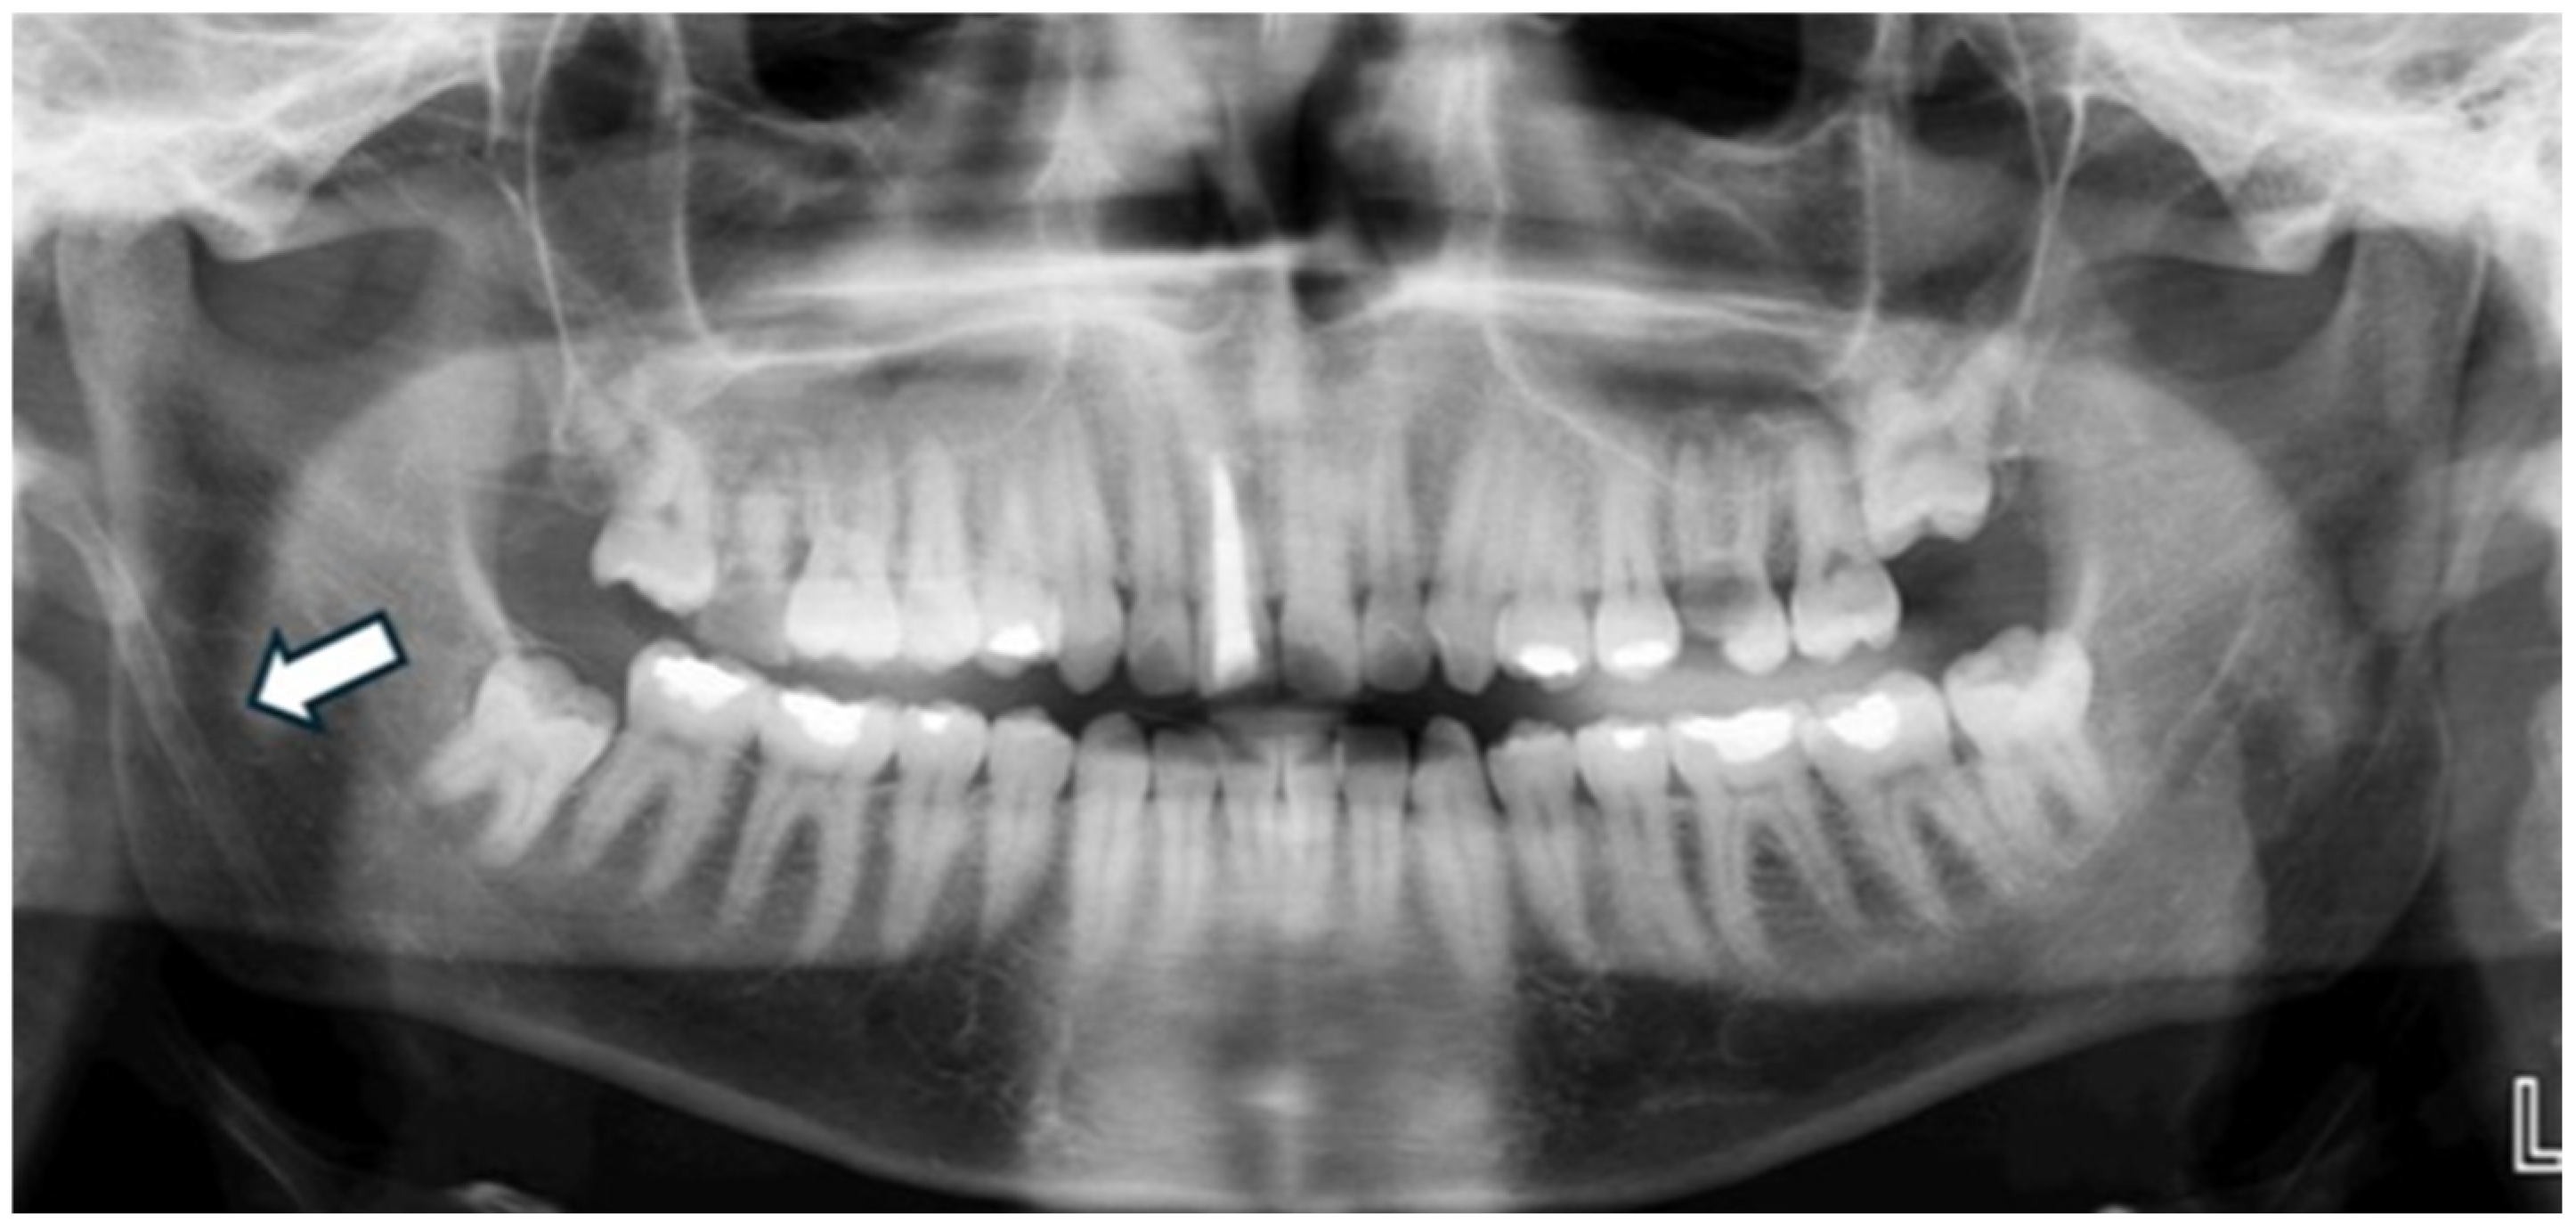

Figure 3. Panoramic radiograph of a 36-year-old male patient showing a well-defined radiopaque mass superimposed over the left mandibular ramus region, consistent with a tonsillolith.

Regarding the overall frequency of each calcification type among the 122 affected patients, styloid ligament ossification emerged as the most prevalent finding, accounting for 31 cases (25.41%) of all detected anomalies (as visually represented in Figure 2). Conversely, anthrolith was the least frequently encountered, with only two cases (1.64%) identified. Other prominent calcifications included laryngeal cartilage calcification (28 cases, 22.95%), tonsillolith (25 cases, 20.49%, illustrated in Figure 3), calcified lymph node (18 cases, 14.75%, depicted in Figure 4), and calcified atherosclerotic plaque (18 cases, 14.75%). It is pertinent to highlight that a thorough investigation for other commonly reported calcifications/ossifications within the head and neck region, such as arteriosclerosis, phleboliths, and sialoliths, yielded no positive findings throughout our study population.

Dystrophic calcification, stemming from chronic tonsil inflammation, is termed tonsillolith. On panoramic imaging, it typically manifests as one or several small radiopacities superimposed on the middle portion of the ramus height [36]. Reported frequencies of tonsilloliths on PRs span a range between 1.45% and 8.14% [24,37]. In our investigation, we identified tonsilloliths in 25 cases, representing a prevalence of 20.49%. This rate is notably higher than figures commonly reported in the literature, which typically fall within the 1.45% to 8.14% range. This significant disparity warrants further exploration and highlights the potential for population-specific variations, differences in diagnostic criteria, or improved detection capabilities in our study cohort.